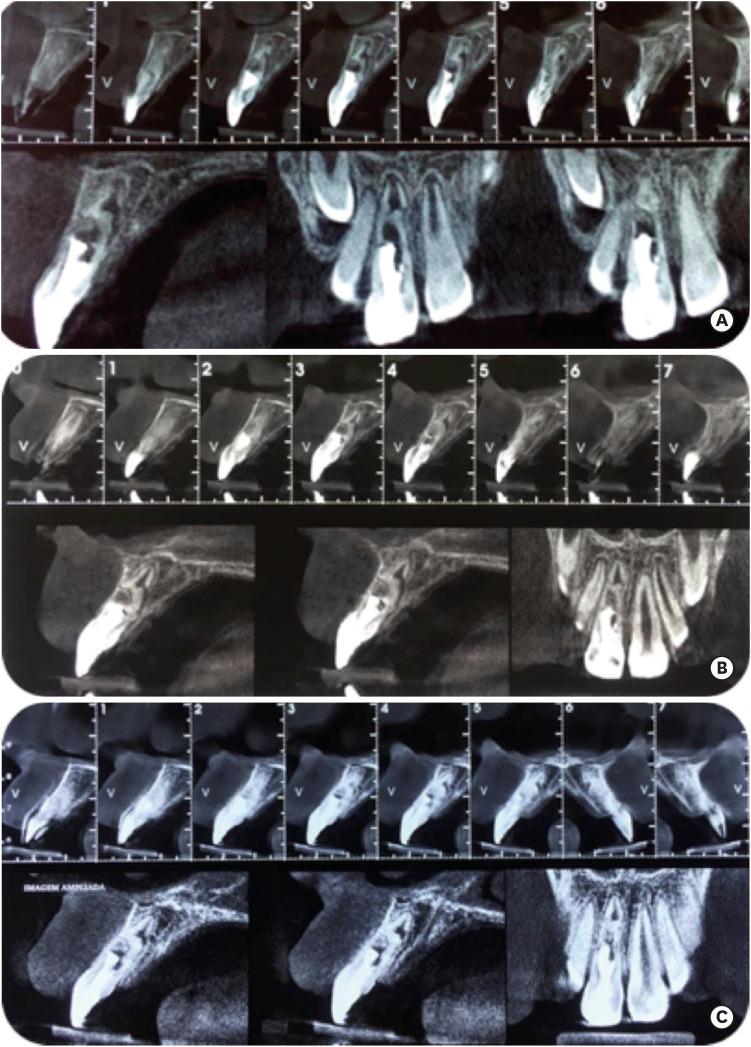

This study describes the clinical steps taken in the treatment of a patient who had an avulsed right upper central incisor that presented with incomplete root development and chronic apical periodontitis. A 7-year-old boy was referred from a private dentist to a dental office specializing in endodontics. The tooth had remained in a dry environment for 20 minutes, and tooth replantation was performed at an emergency appointment. After clinical and radiographic examinations, root canal decontamination was performed, followed by several changes in intracanal calcium hydroxide medication. Blood clot formation was attempted, but bleeding within the root canal was insufficient; therefore, we opted for an intracanal medication change to stimulate mineralized tissue formation in the apical region. Root obturation was performed 45 days after the last change of intracanal medication, and clinical, radiographic, and tomographic follow-up examinations were performed at 3, 6, 18, and 40 months after the endodontic intervention. The increase in thickness and length of the root structure and the absence of root resorption were verified through follow-up examinations. Therefore, it was concluded that the procedures used were successful for tooth replantation.

本研究描述了对一名右上中切牙脱位患者的治疗临床步骤,该患者存在牙根发育不全及慢性根尖周炎。一名7岁男孩从私立牙医处转诊至一家牙髓病专科牙科诊所。该牙齿在干燥环境中存留了20分钟,在急诊预约时进行了牙齿再植。经过临床和影像学检查后,进行了根管消毒,随后多次更换根管内氢氧化钙药物。尝试形成血凝块,但根管内出血不足;因此,我们选择更换根管内药物以刺激根尖区域矿化组织形成。在最后一次更换根管内药物45天后进行了根管充填,并在牙髓治疗干预后的3、6、18和40个月进行了临床、影像学和断层扫描随访检查。通过随访检查证实了牙根结构厚度和长度的增加以及牙根吸收的未出现。因此,得出结论,所采用的程序对于牙齿再植是成功的。